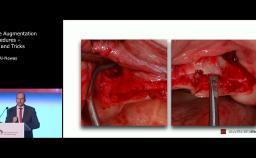

The Expanded Edentulous Space in the Anterior Maxilla – Surgical Considerations

Stephen Chen discusses the challenges that surgeons face when looking at dental implant solutions for the rehabilitation of patients with extended edentulous spaces in the anterior maxilla. He covers anatomical and surgical considerations both from a theoretical and practical point of view, using a clinical case to illustrate the topic.